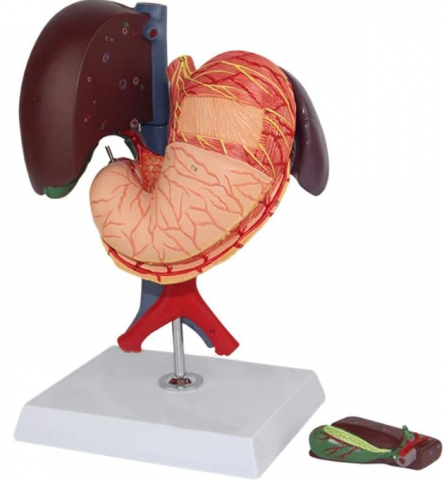

Modelul este conceput din material plastic PVC și este frumos colorat.

Acest model este conceput ca ajutor vizual pentru predarea cursurilor de anatomie umană și igienă. Este folosit pentru a demonstra structura dintelui, la studiul sistemului digestiv în gimnaziu, liceu și școli postliceale medicale.

Acest model are înălțimea de 23-26 cm, prezintă 3 rădăcini, o secțiune longitudinală prin care se poate observa structura interioara a dintelui, este conceput din material plastic PVC și este frumos colorat.